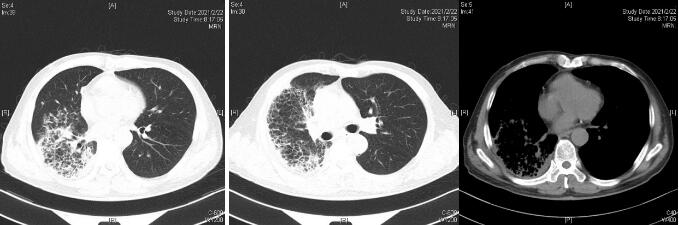

患者经过近1周治疗,临床症状较前好转,心衰纠正,炎症指标明显下降,于1月31日体温正常后转普通病房。感染方面美平降级为头孢派酮舒巴坦,继续多西环素治疗。2月2日外送标本DNA测序鉴定为Balneatrix alpica,即阿尔卑斯浴者菌。后续患者出现胸膜炎性胸痛,间断气促,复查肺部CT提示右侧胸腔积液量增多,给予穿刺引流,胸水外送经DNA鉴定报高山巴氏发菌,即Balneatrix alpica,至此患者感染的病原菌明确,考虑此菌为少见菌,对抗菌药物敏感性较高,后续抗生素方案降解为左氧氟沙星500 mg/d,经治疗3周后患者出院,后期随访追踪无不适。

| 图 3 2月22日出院胸部CT平扫 |